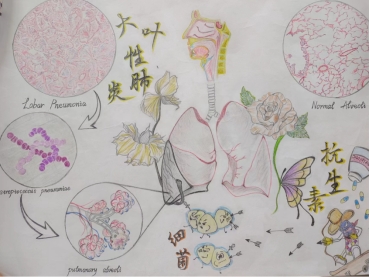

作品名:《大叶性肺炎的病因与防治》

作品简介: 大叶性肺炎主要是由于机体抵抗力减弱,使得肺炎链球菌侵入肺泡而发病,且多发生于单侧肺下叶。作品描绘的是大叶性肺炎的灰色肝样变期,通过盛放和衰败的花朵来分别表示肺的健康与疾病,并在左右两侧附上病变肺泡与正常肺泡的显微结构,便于更加直观清晰的比较两者的差异。同时,下方运用拟人手法,告知大家在疾病早期运用抗生素治疗的必要性,希望由此引起大家对这类细菌性疾病的关注与重视,养成健康的生活方式,保护好自己的身体。